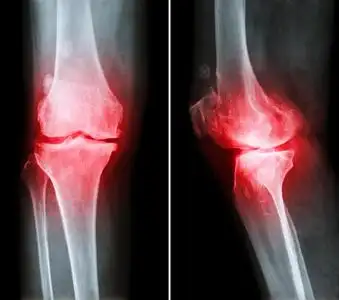

薄膜 x 射线膝盖 (前-后, 侧视图) 显示关节间隙狭窄, 骨赘 (骨刺)

膝关节骨刺处理